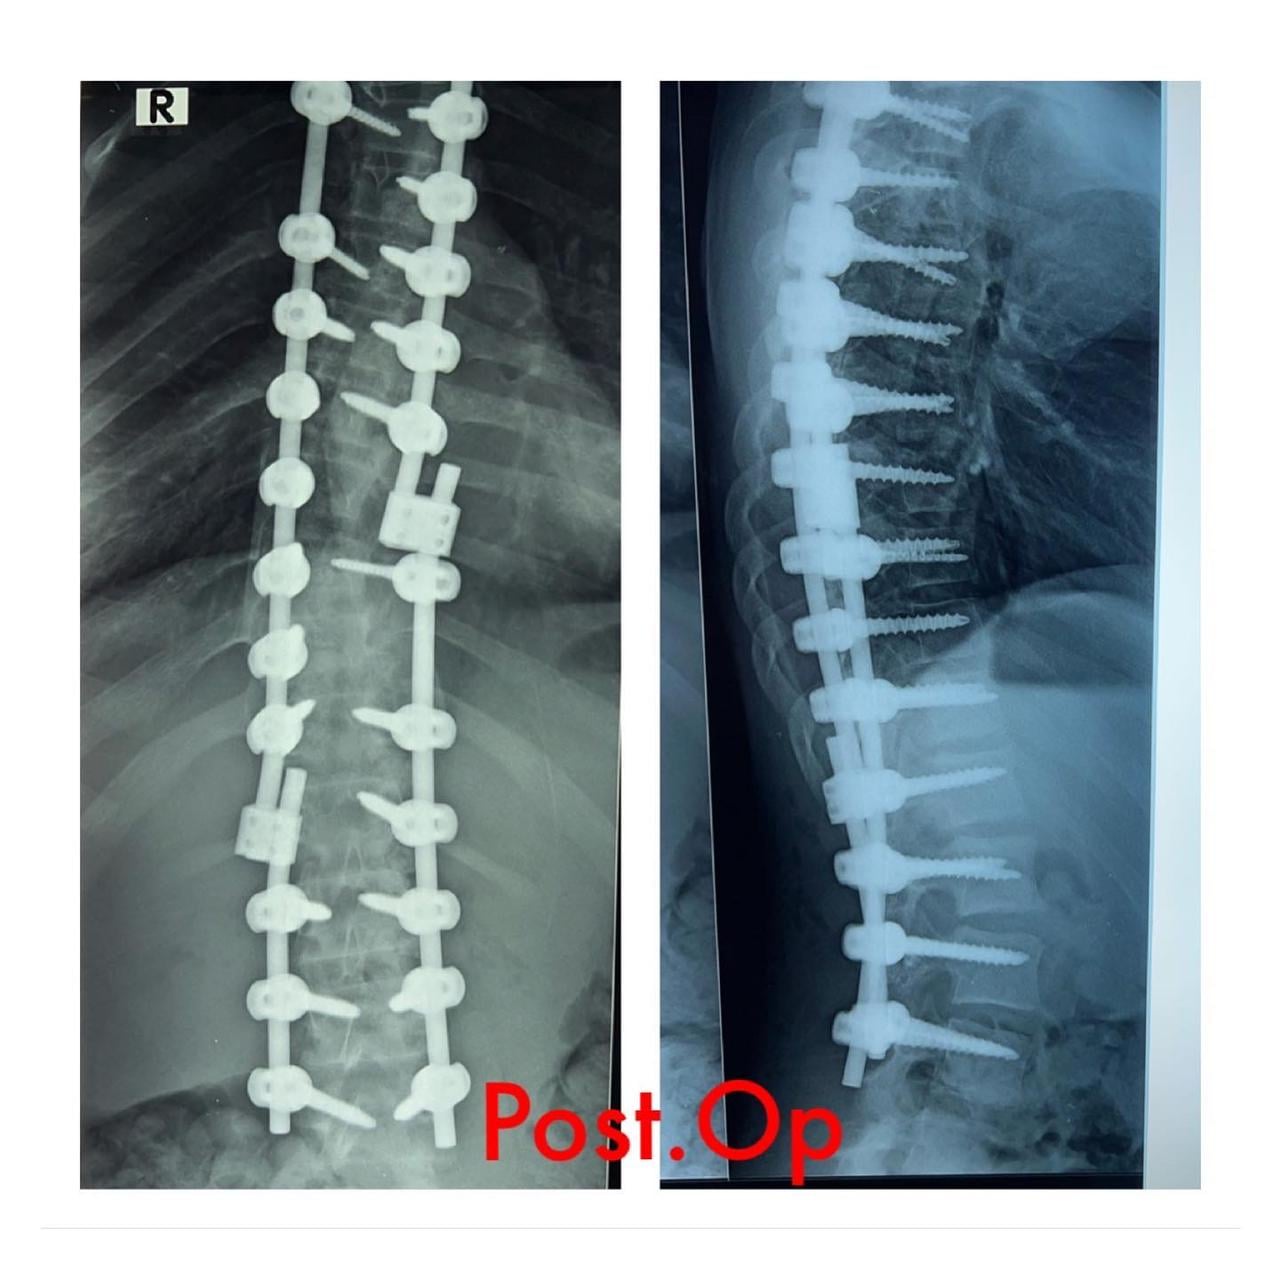

Azərbaycan Tibb Universitetinin Tədris Cərrahiyyə Klinikasında skolioz diaqnozu qoyulmuş 12 yaşlı uşaq cərrahi əməliyyat olunub. Əməliyyat klinkanın Neyrocərrahiyyə şöbəsinin assistenti Cəmil İskəndərovun rəhbərliyi ilə həyata keçirilib.

Aztibb.az xəbər verir ki, neyrocərrahın bildirdiyinə görə, uşaqda skolioz xəstəliyi 10 yaşında aşkar olunub: “Xəstə son dövrlər korsetdən istifadə etməsinə baxmayaraq, onda sürətlə əyilmə prosesinin getməsi müşahidə edilirdi. Əyilmə 45 dərəcədən artıq idi. Prosesin qarşısını almaq mümkün olmadığı üçün onu əməliyyat etməyi qərara aldıq. Sevindirici haldır ki, əməliyyat uğurlu həyata keçdi. Artıq ertəsi gün xəstə gəzdirildi. Vəziyyəti qənaətbəxş olduğu üçün 4 gündən sonra evə yazıldı. O, hazırda özünü normal hiss edir”.

Həkim ağır əməliyyat olmasına baxmayaraq uşağın onurğasının tez bir zamanda bərpa olunacağına, normal həyata dönəcəyinə və təhsilini davam etdirəcəyini diqqətə çatdırıb.